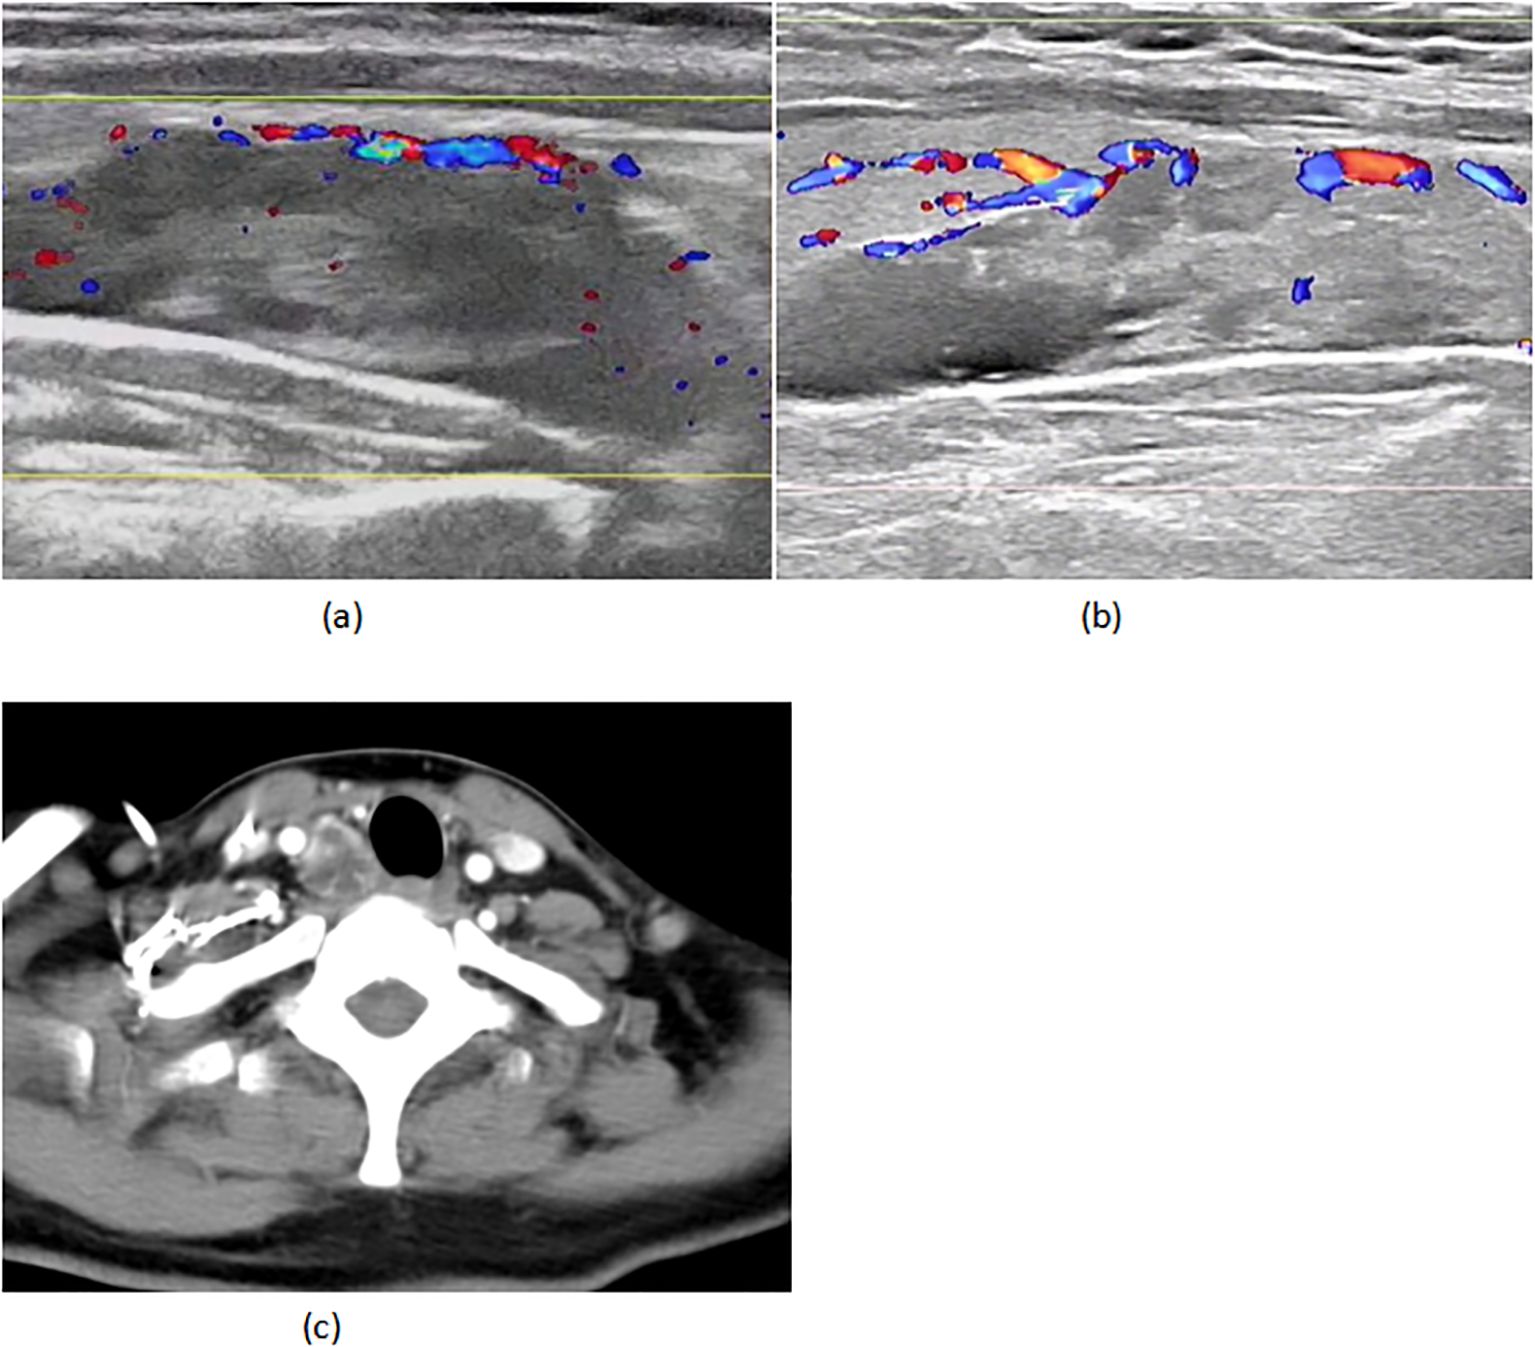

A 45-year-old woman with triple-negative breast cancer (cT3N1M0, stage IIIA) initiated neoadjuvant therapy (nab-paclitaxel/carboplatin/pembrolizumab) in March 2024. She achieved clinical partial response (cPR) after two well-tolerated cycles. Baseline evaluation revealed a right parathyroid mass (38×13mm, negative biopsy) (Figure 1A) with mild hypercalcemia (2.90 mmol/L; normal 2.10-2.60) and elevated iPTH (15.46 pmol/L; normal 1.6-6.9), suggesting parathyroid dysfunction.

Figure 1

(A) 02–29 parathyroid ultrasound (B) 05-18 parathyroid ultrasound (C) 05–18 CT of the neck.